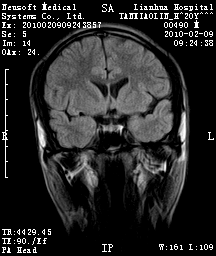

20岁男性患者,平时偶有头痛而无其他不适,现因持续头痛服药后无缓解而来院就诊。

松果体区占位继发轻度脑积水?该患者有ct资料,我已发上。

考虑松果体囊肿。

松果体囊肿?